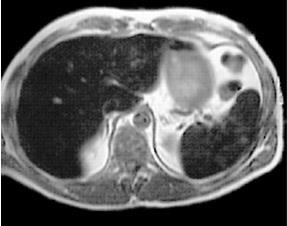

Egy egyszerű ciszta máj

1. Egyszerű - azzal jellemezve, vékony falak, falak nélkül, egy homogén folyadék tartalmát.